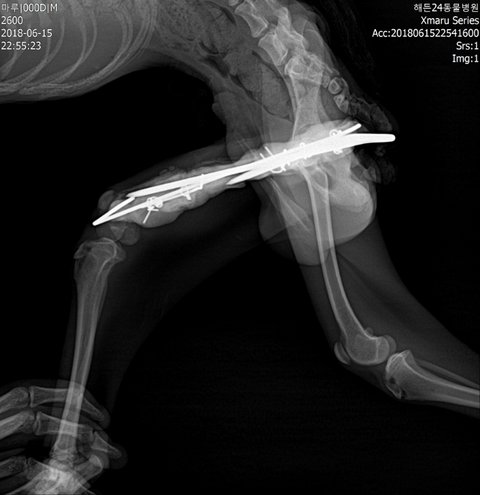

몸무게2.8키로/PSS(소간증)/예전홍역의심/골절수술부위2차감염/빈혈/탈수/저체중/저체온/눈궤양/암모니아,신장,칼슘,거의 모든수치 이상/이빨멜라닌색소소멸/위장음식물없음등을 알게됐습니다.

다리는 골수염으로 염증이 심각했고, 절단가능성이 계속 이야기되었지만 기적적으로 염증을 6ml 뽑아낸후 항생제 예후가 좋아 다행히 좋아지고있는 상태입니다. 하지만 아직 금이 가있고 내원치료중입니다..

초진 엑스레이입니다.